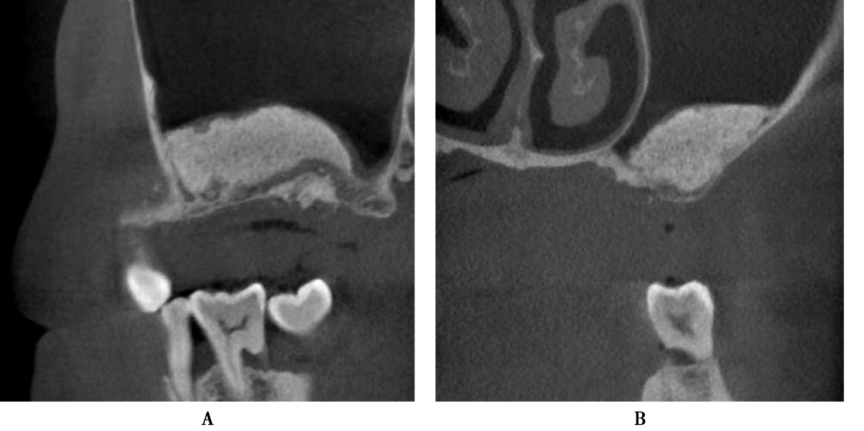

术前CBCT示剩余牙槽骨高度约3mm,近远中距离约10mm,宽度大于8mm,上颌窦内清澈无炎症,上颌窦底黏膜约2mm(图1B,C)。为保证植骨效果,拟进行上颌窦侧壁开窗外提升并同期植入种植体。

图1 A6缺失,CBCT示剩余牙槽骨高度3mmA.口内观;B.矢状面;C.冠状面

术前CBCT显示缺牙区牙槽嵴顶到上颌窦底的最小高度约3mm,上颌窦底黏膜约1mm,上颌窦腔影像清澈,无炎症,侧壁厚度1~2mm(图12)。

图12 术前CBCTA.冠状面;B.矢状面